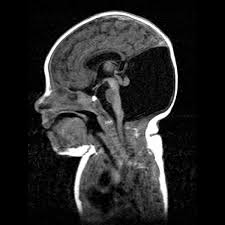

Trisomy 14